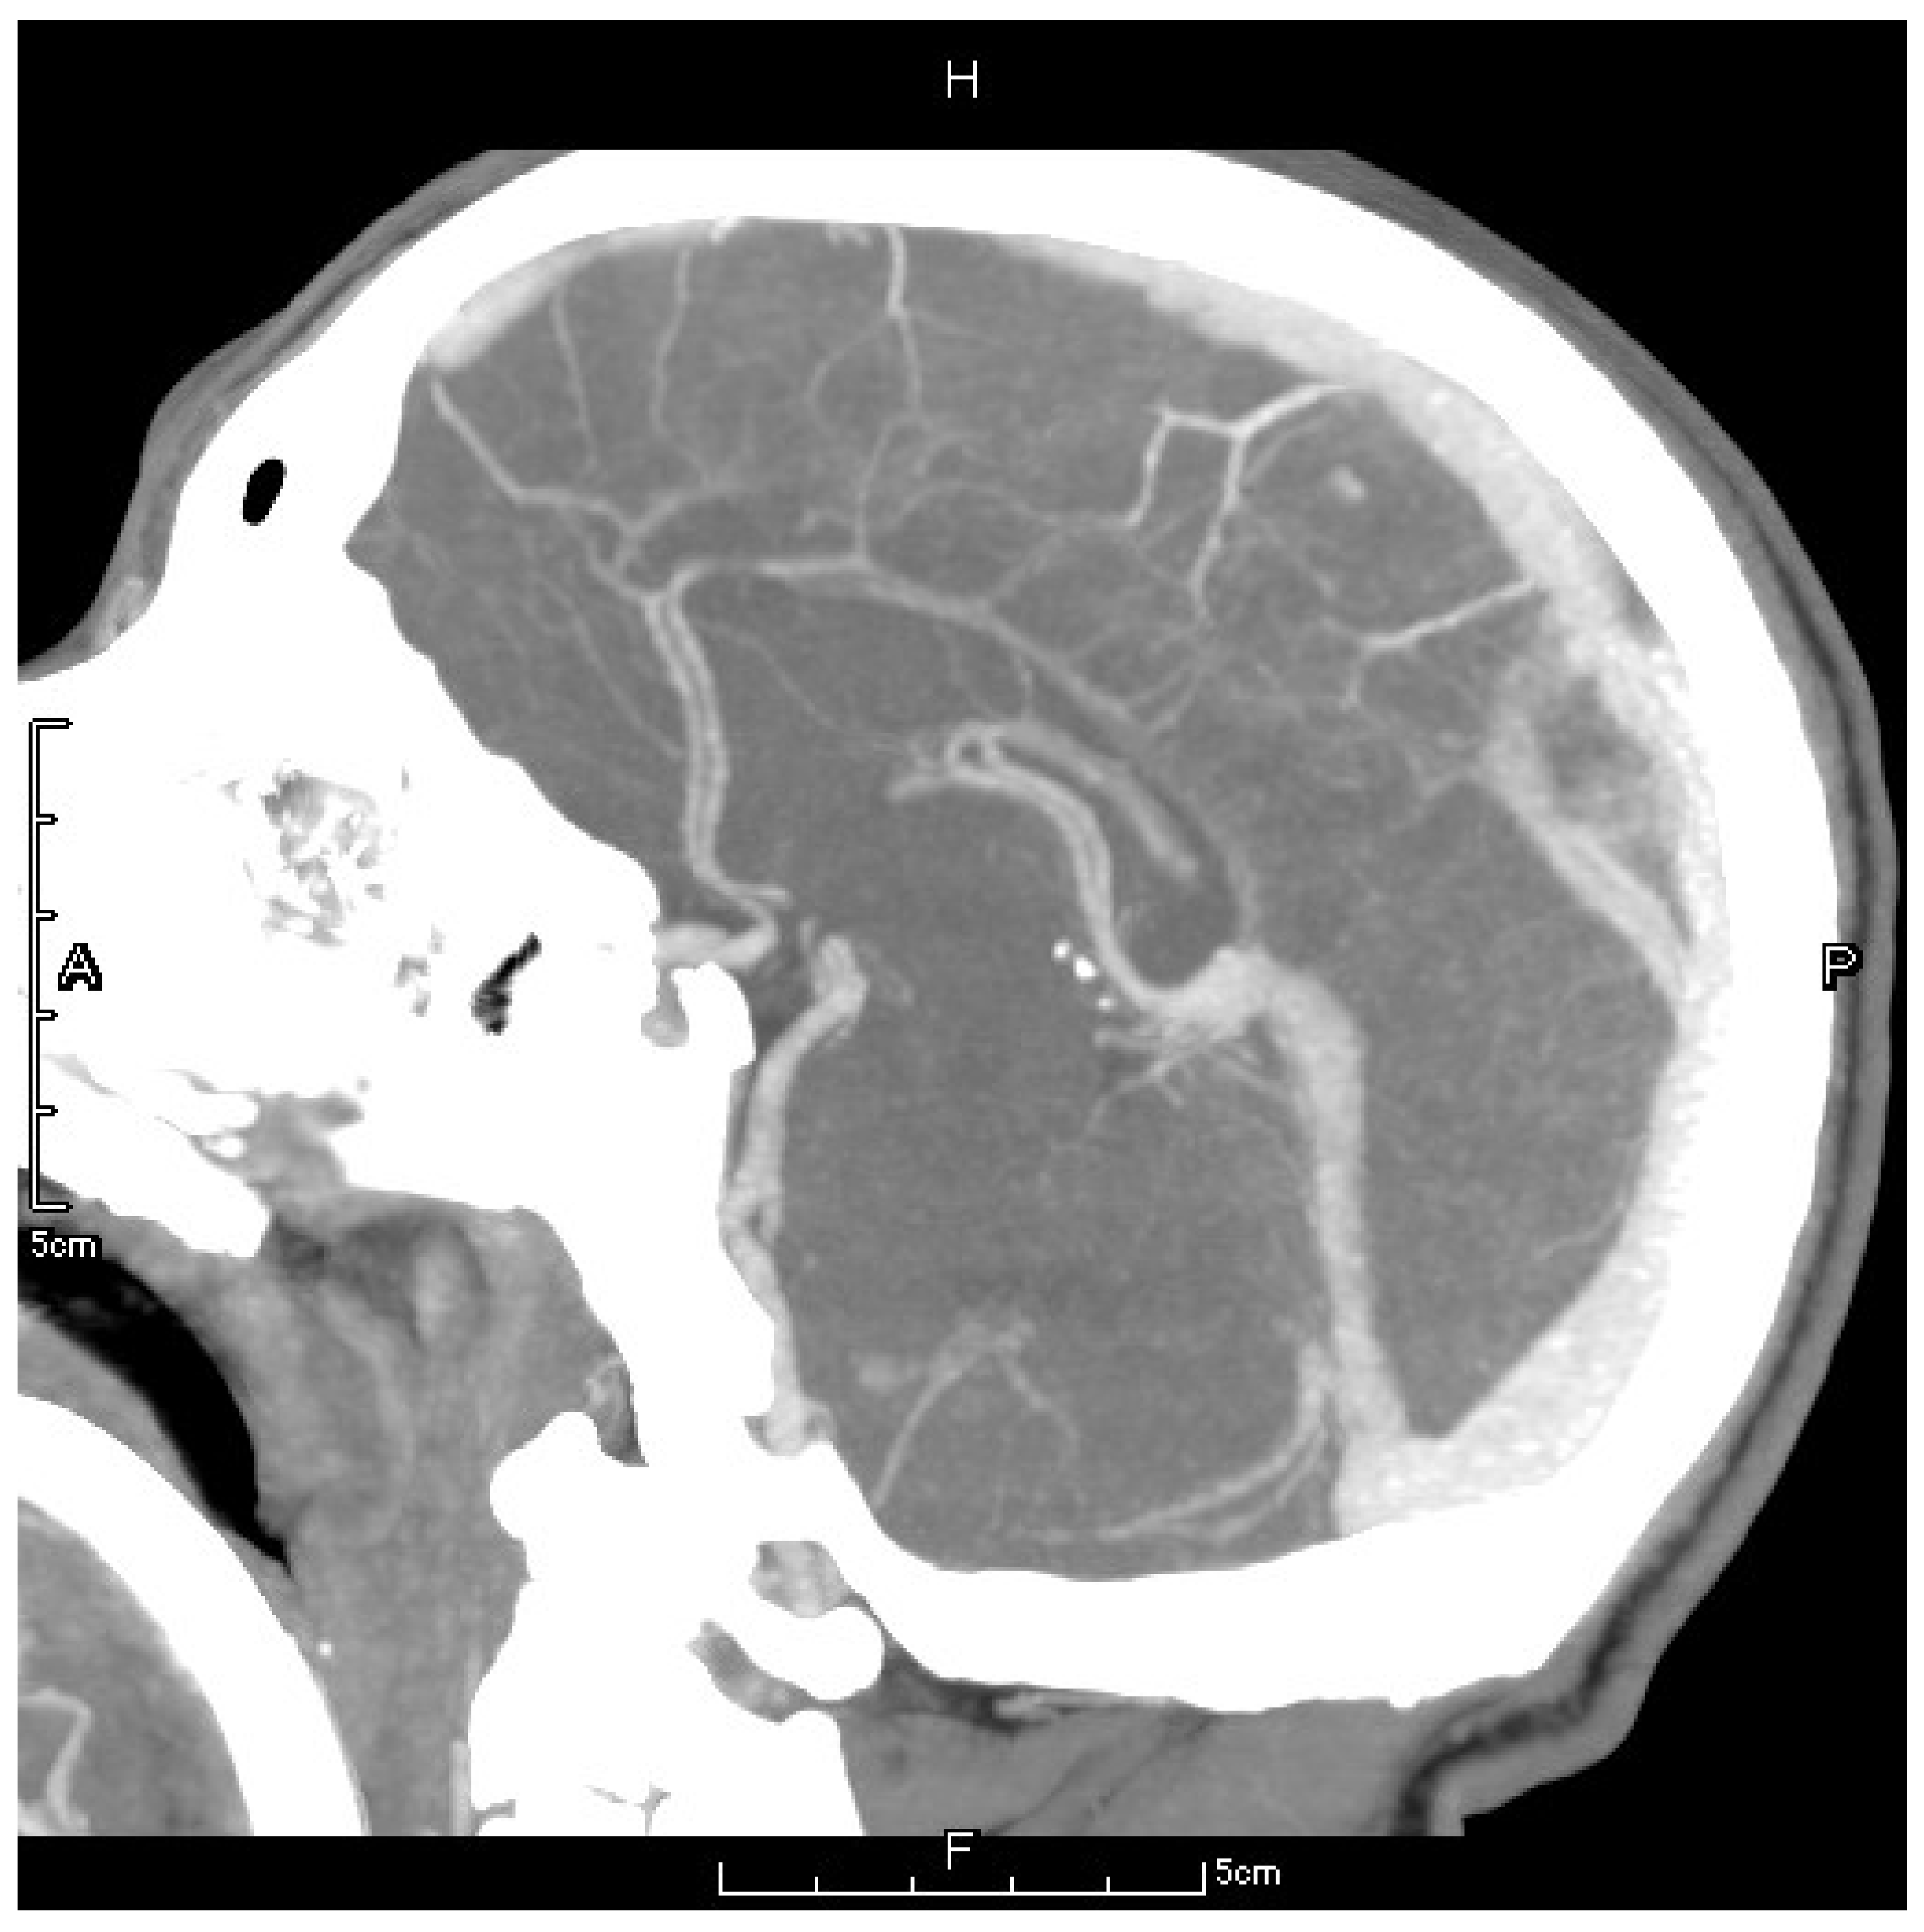

Figure 3.

The letter F, A, P, H in the figures refers to Foot, Anterior, Posterior and Head, respectively. Preoperative CTV showed a local patchy filling defect shadow behind the superior sagittal sinus which should be considered as thrombus formation.

Under general anesthesia and electrocardiogram monitoring, the patient was placed in the supine position and routine disinfection and draping of the surgical area were performed. The puncture needle was pierced into the right femoral artery using the modified Seldinger technique. Then, a 5F radial artery special-purpose puncture sheath was inserted. Through angiography, a 20 mm filling defect was observed at the superior sagittal sinus with slow blood velocity, which could be considered a thrombus formation at the superior sagittal sinus. Then, the right jugular vein was punctured using the modified Seldinger technique, and a 6F radial artery special-purpose puncture sheath was inserted. Next, the guidewire was delivered to the superior sagittal sinus thrombus, and the stent was delivered along the microcatheter to the thrombus and released for thrombus retrieval. The thrombus was subsequently extracted. Finally, post-embolization imaging suggested complete superior sagittal sinus recanalization (Figure 4).